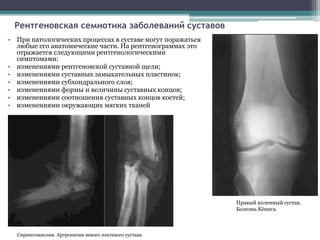

• При патологических процессах в суставе могут поражаться

любые его анатомические части. На рентгенограммах это

отражается следующими рентгенологическими

симптомами:

• изменениями рентгеновской суставной щели;

• изменениями суставных замыкательных пластинок;

• изменениями субхондрального слоя;

• изменениями формы и величины суставных концов;

• изменениями соотношения суставных концов костей;

• изменениями окружающих мягких тканей

Правый коленный сустав.

Болезнь Кёнига.

Сирингомиелия. Артропатия левого локтевого сустава